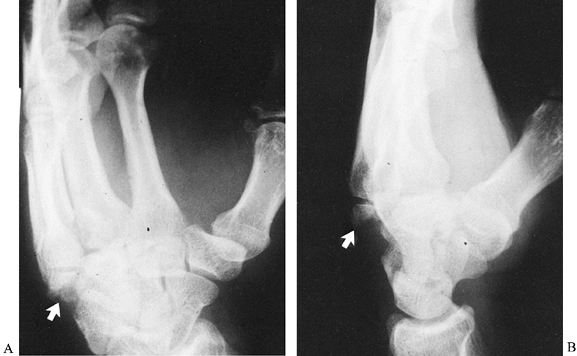

Figure 42.15. A,B:

Conventional lateral and posteroanterior views of the wrist in a

patient with Kienböck’s disease and an ulna minus deformity. The

integrity of the lunate could not be determined by conventional

radiographs. C: Lateral tomography clearly

shows that the lunate had fragmented. This view also demonstrates the

usefulness of tomography for visualizing the hamate bone and its hook (arrow). -